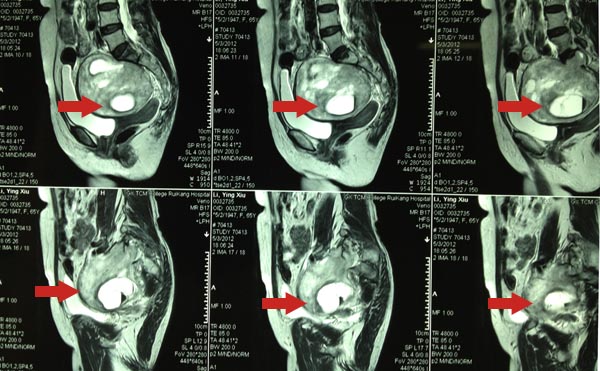

骨脊柱一区陈远明主任,陈锋主任,周先明及黄民锋副主任详细了解患者病情后,结合本院的盆腔MRI增强及盆腔彩超提示:盆腔内肿物混合性回声,肿物约11×9×10cm大小,考虑神经源性肿瘤?另胃肠外科、肿瘤科、妇科等科室会诊后都建议尽快手术治疗,了解肿物性质。陈远明主任集中科室成员意见后,考虑该肿物为神经源性,首先考虑脊索瘤,该瘤好发于颅底及骶尾部,为低度恶性的肿瘤,切除后易复发,一般术后需放疗;畸胎瘤也不能排除,该瘤中可能出现头发、骨组织等;还有可是罕见的巨大神经鞘瘤,该瘤属于良性。结合患者目前身体状况,认为肿物过大与周围组织粘连,重要血管分布集中,肿物蒂部血管丰富,术中出血量多,采用前路经腹膜外切口切除肿物。陈远明主任及周先明副主任亲自主刀,手术过程顺利,肿瘤重量约1000g左右。

术前CT